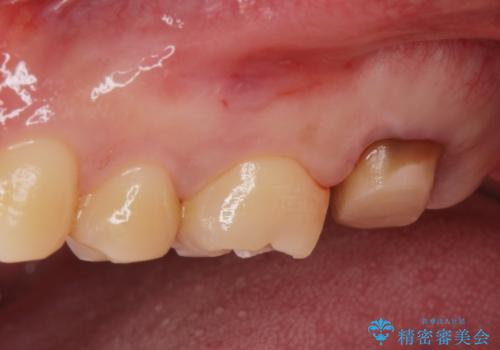

- 銀歯を良いものに変えたいとの事で来院。

過去に根の治療もされている歯だが土台が粗造なため根の治療からやり直しを行いゴールドクラウンにて治療を行いました。

また手前のはに虫歯があったためセラミックの詰め物で治療しました。